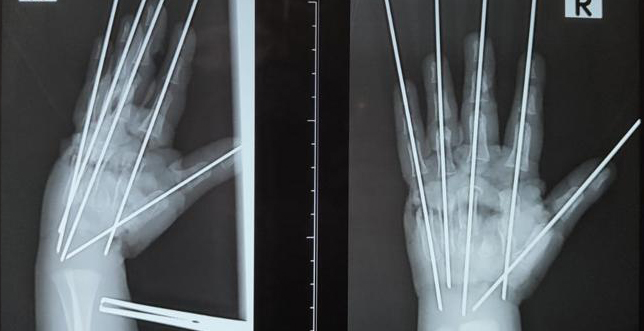

– Травма очень тяжёлая, что обусловлено раздавливающим механизмом мясорубки. Повреждена была вся кисть, раздроблены кости, сухожилия, сосуды, нервы. Фактически имела место ампутация – кисть держалась на нескольких связках. Нашей задачей было сохранить жизнеспособные ткани, восстановить анатомию конечности и кровообращение, – сообщил врач. |

В ходе операции специалисты Педиатрического университета буквально собрали по частям травмированную руку мальчика.

– Мы выполнили металлоостеозинтез, чтобы соеденить осколки костей. Затем было необходимо восстановить кровоснабжение кисти, – рассказал Антон Волков. |

Ребёнку потребовалась аутовенозная пластика: размозженный участок локтевой артерии хирурги заместили фрагментом подкожной вены пациента. Медики отметили, что после этого пальцы ребёнка стали понемногу розоветь.